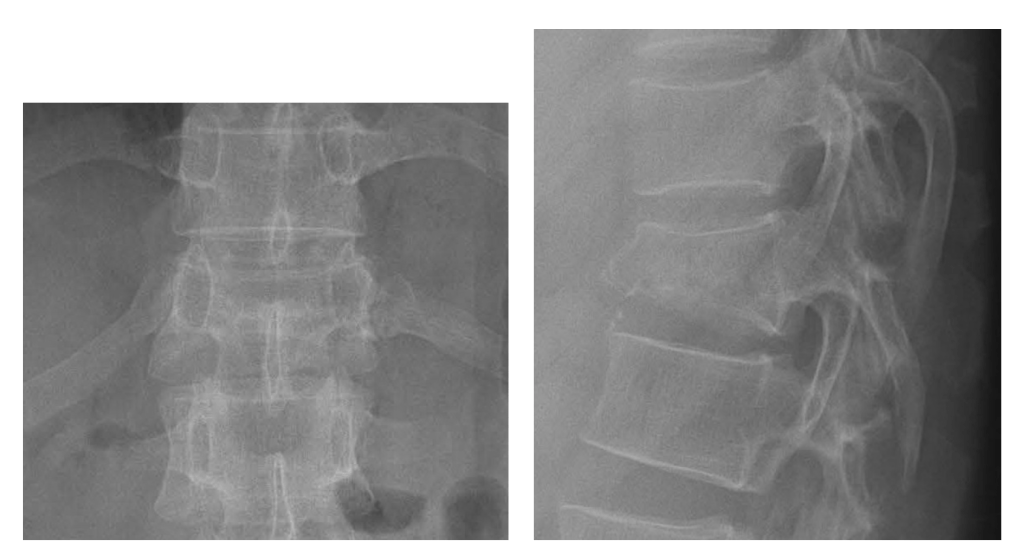

การฉีดซีเมนต์ยึดกระดูกสันหลังวิธีนี้ สามารถรักษาอาการปวดหลัง จากภาวะกระดูกสันหลังแตกยุบได้ แต่ไม่สามารถถ่างขยายกระดูกสันหลังที่แตกยุบ ให้คืนสู่ขนาดใกล้เคียงปกติ ทำให้บริเวณที่ยุบมีการโก่งเอียงจนแนวหลังผิดปกติถาวรได้(Kyphosis) จึงมีอีกทางเลือก คือ การฉีดซีเมนต์ยึดกระดูกสันหลัง ด้วยการยกถ่างกระดูกสันหลังที่แตกยุบด้วยบอลลูน(Balloon Kyphoplasty) วิธีนี้ สามารถยกความสูงของกระดูกสันหลังที่แตกยุบให้สูงขึ้นในระดับที่ใกล้เคียงกับระดับปกติ โดยใช้บอลลูนขยายหรือเครื่องมือช่วยถ่างขยายใส่เข้าไปภายในกระดูกสันหลังที่แตกยุบ ผ่านเข็มที่ใช้ฉีดซีเมนต์ แล้วจึงฉีดซีเมนต์ยึดกระดูกสันหลัง

นอกจากนี้จะช่วยยกส่วนที่แตกยุบของกระดูกสันหลังให้คืนสู่ขนาดใกล้เคียงปกติ และยังทำให้ฉีดซีเมนต์ได้ปริมาณมากกว่าวิธีไม่ใช้บอลลูน (Vertebroplasty) โดยที่การรั่วของซีเมนต์น้อยกว่า ทำให้กระดูกสันหลังที่แตกยุบแข็งแรงมากกว่า และอาจแก้ไขภาวะกระดูกสันหลังโก่ง (Kyphosis) ในระดับที่มีกระดูกสันหลังแตกยุบได้

กล่าวโดยสรุปคือ การฉีดซีเมนต์ยึดกระดูกสันหลังเป็นวิธีการรักษาภาวะกระดูกสันหลังแตกยุบที่ได้ผลดี เจ็บแผลผ่าตัดน้อยมาก ผู้ป่วยหายปวดหลังได้เร็วและสามารถฟื้นตัวกลับไปใช้ชีวิตประจำวันได้ตามปกติในระยะเวลาสั้น นอกจากนี้ยังป้องกันภาวะกระดูกสันหลังโก่งค่อมที่อาจตามมาหลังจากรักษากระดูกสันหลังที่แตกยุบด้วยวิธีไม่ผ่าตัดและรอให้กระดูกติดเอง

ตัวอย่างผู้ป่วยที่ได้รับการฉีดซีเมนต์ด้วยวิธียกถ่างกระดูกสันหลังที่แตกยุบด้วยบอลลูน